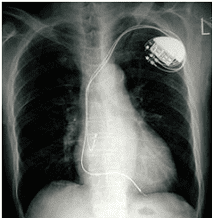

ペースメーカー移植術の一例

-

| ペースメーカー移植術 (経静脈電極) |

23 | 19 | 16 |

| ペースメーカー交換術 | 12 | 12 | 11 |